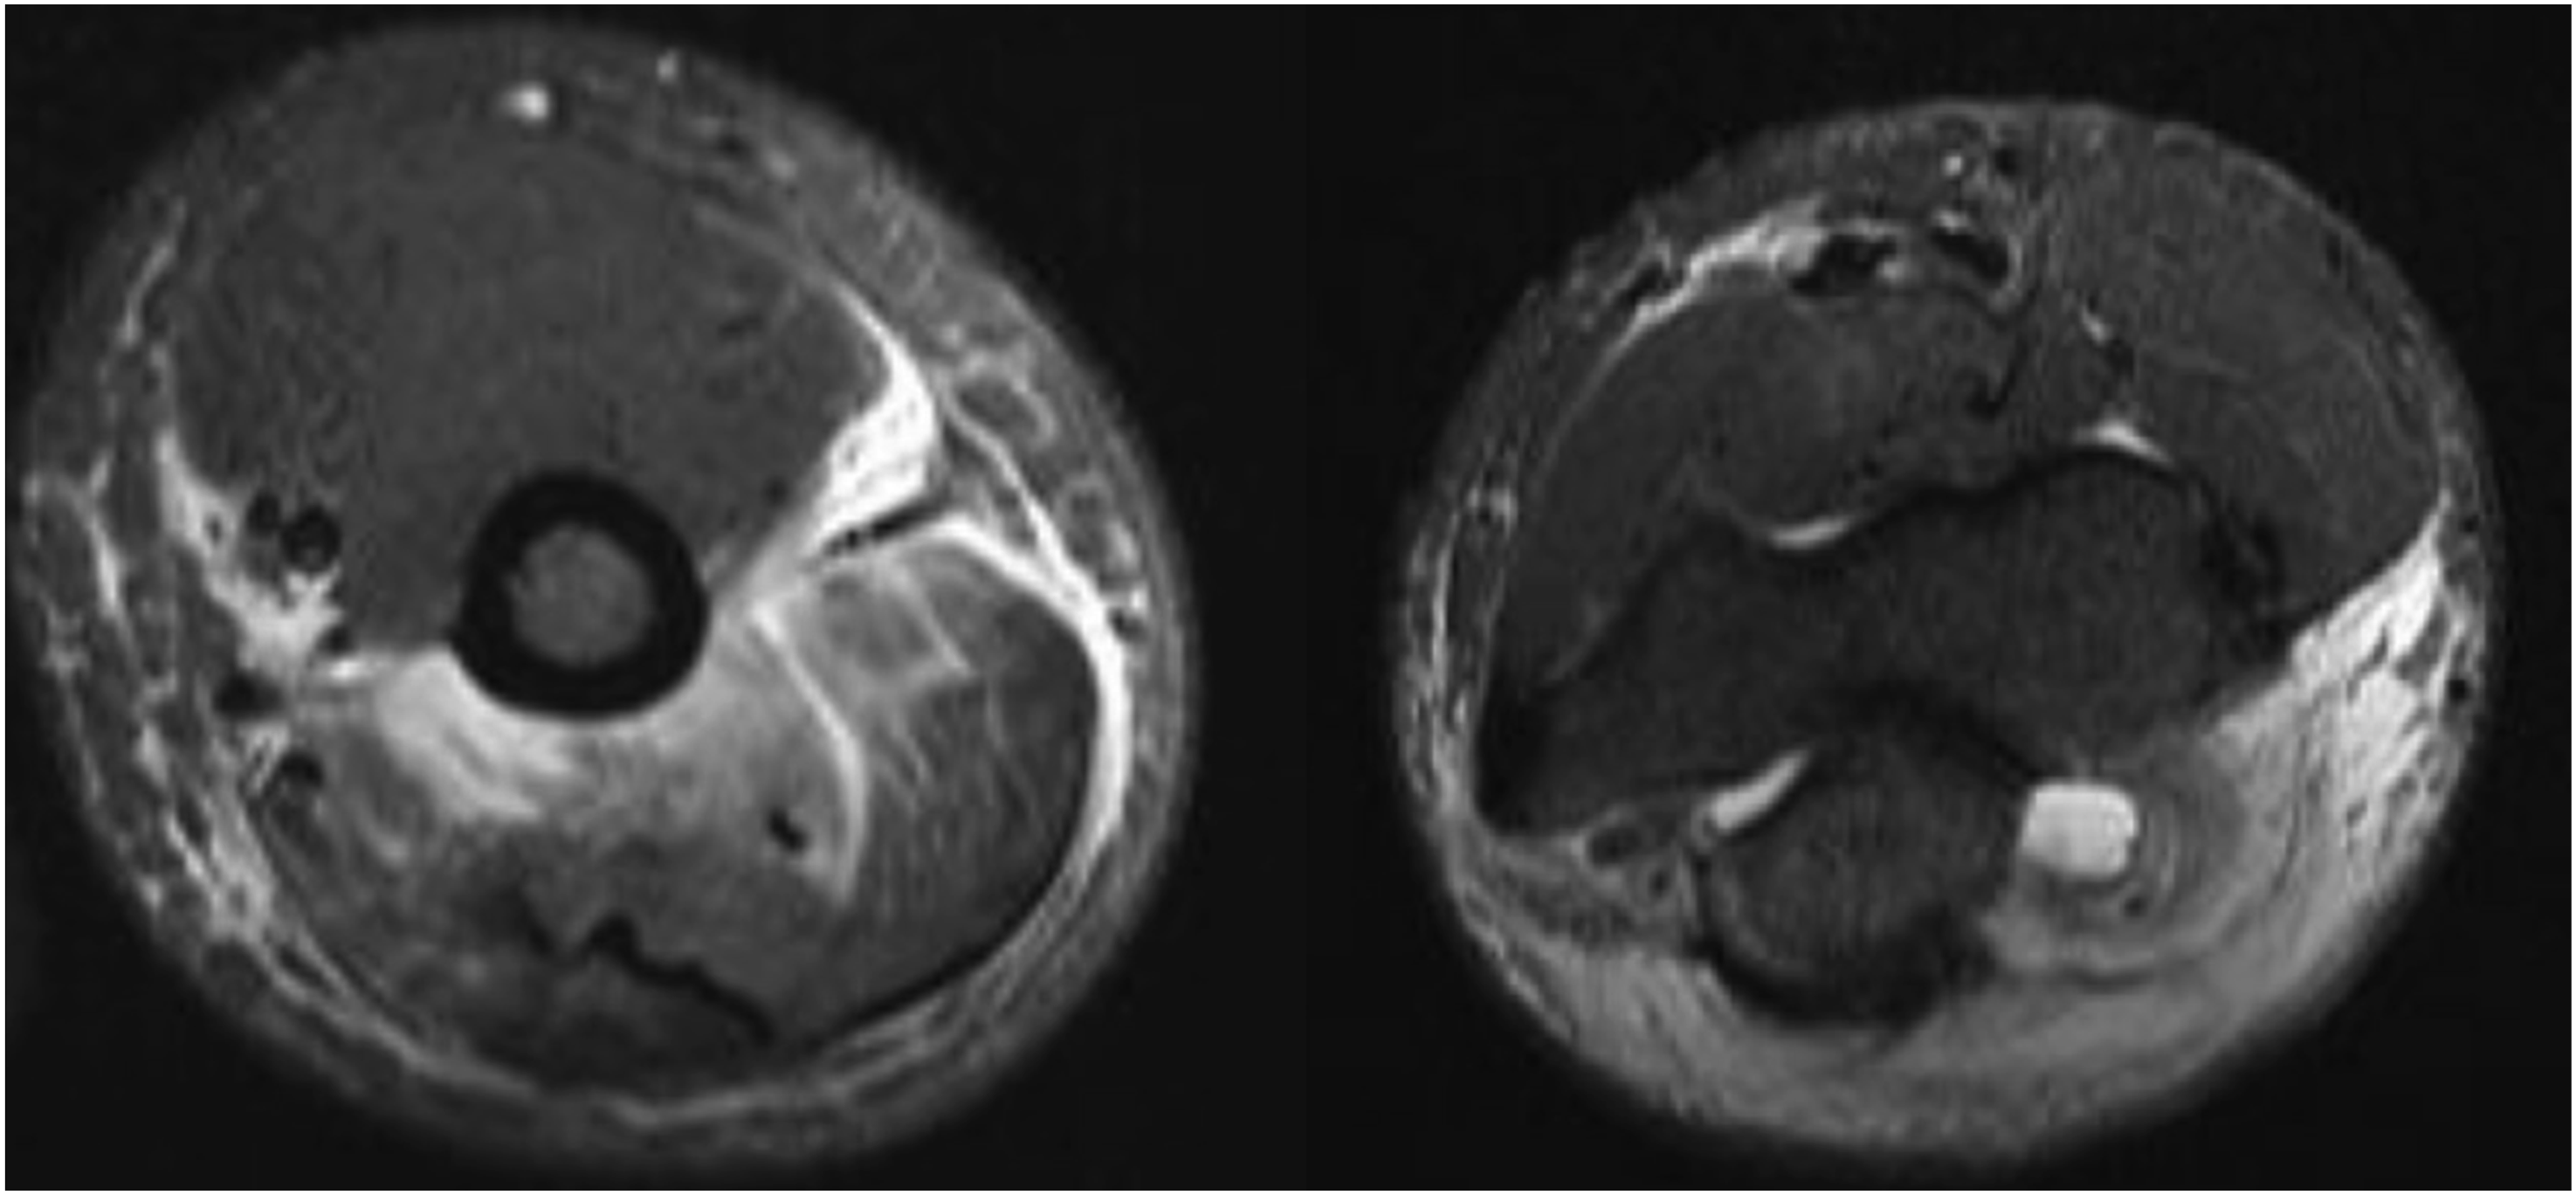

Two months later, he developed new-onset migratory polyarthritis involving the left elbow, bilateral ankles, knees, and small joints of both hands. At this time, the patient did not have any abdominal symptoms. Physical examination revealed joint swelling and tenderness. Radiographs of the right hand (Figure 1) and left elbow (Figure 2) obtained at this time demonstrated only soft tissue swelling, with no radiographic evidence of erosive or inflammatory arthritis, focal bone lesions, or bone infarction. MRI of the left elbow showed posterior subcutaneous and soft tissue edema with associated triceps muscle edema, a small joint effusion and mild bone marrow edema at the olecranon process (Figure 3). Synovial fluid aspirated from the left elbow showed mildly elevated white blood cell count (3000 cells/mm3), but Gram stain, culture, and crystal analysis were negative. Laboratory tests showed elevated ESR and CRP, normal serum uric acid, creatine kinase, and complement (C3 and C4) levels. Antinuclear antibody and rheumatoid factor were negative. Urine tests for Radiographs of the right hand demonstrating soft tissue swelling predominantly about the metacarpophalangeal joints. No osseous erosions, no focal lytic or sclerotic bone lesion. Radiographs of the left elbow demonstrating mild soft tissue swelling at the posterior elbow. No osseous abnormalities. Axial STIR MR images of the left elbow demonstrate subcutaneous edema, triceps muscle edema, small joint effusion and mild bone marrow edema at the olecranon process.